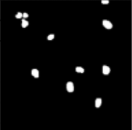

Our results reveal considerable as shown in Figures 6, 7 and 8 respectively and it provides an assurance, as well as at a basic level the algorithm works well, which is shown by the success of the initial prediction.

Figure 6. Training image

Figure 7. Image masking

Figure 8. Predicted image mask